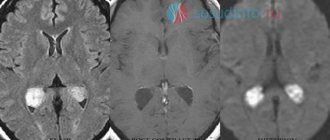

МРТ диагностика при арахноидальной кисте

Несмотря на то, что КТ позволяет точно определить размеры и расположение кисты, наиболее точную и полную информацию об образовании дает МРТ. Обычно для диагностики арахноидальной кисты проводится МРТ-сканирование с введением в кровоток пациента контраста. При этом опухоли мозга имеют свойство накапливать контраст, а кисты не впитывают его из кровеносных сосудов, что очень четко видно на МРТ.

Также МРТ-сканирование позволяет отличить кисту от кровоизлияний, гематом, гигром, абсцессов и других заболеваний со сходной симптоматикой. Кроме того, МРТ дает возможность выявить кисту даже в тех случаях, когда у пациента еще нет никаких проявлений, а сама киста имеет размеры всего в несколько миллиметров.